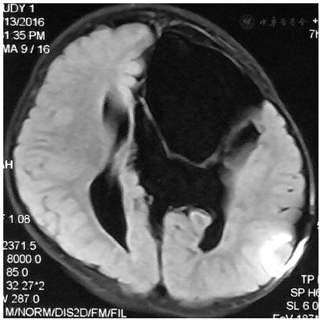

入院后行蛛网膜囊肿-腹腔(Cystoperitoneal,CP)分流术,初始开放压力设定为18 cmH2O,后每间隔3-6月调低2-3 cmH2O;术后2月MRI发现蛛网膜囊肿缩小;术后22月MRI发现囊肿进一步缩小,可见囊肿内分隔和透明隔,进一步行内镜下囊肿分隔和透明隔造瘘术,术后每2-3月逐步将分流阀压力从9 cmH2O调至15cmH2O;造瘘术后3月复查MRI发现囊肿进一步缩小、脑皮层增厚;

患儿行蛛网膜囊肿腹腔分流术后前囟门压力下降,右侧肢体活动有所好转;患儿行内镜下囊肿造瘘术后囊肿进一步缩小、脑皮层增厚,左侧脑组织进一步复张;右侧肢体活动接近正常、肌力V级。

造瘘术后三月复诊复查MRI发现囊肿进一步缩小、脑皮层增厚,左侧脑组织进一步复张,患儿右侧肢体活动较前明显好转、肌力V级。术后7年随访患儿已上一年级,家属诉患儿于学校学习、活动表现无明显异常。